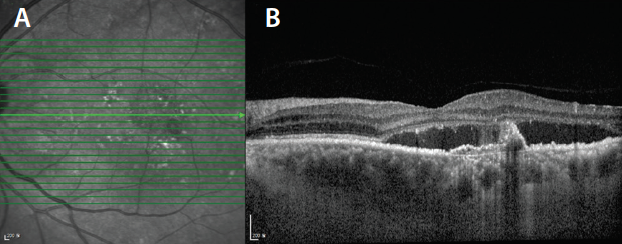

Figure 2. Automated choroidal segmentation (A and B) and binarization (C) of an SS-OCT B-scan of a normal eye.

Choroidal Segmentation and Vessel Layer Thickness

Automated choroidal segmentation and vessel layer thickness analysis provides information on specific choroidal layers in normal eyes and in various disease conditions. For instance, significant thinning of medium choroidal vessels has been noted in nonpathologic myopic eyes.22 Segmentation involves identification of the choroidal inner boundary just below the highly reflective retinal pigment epithelium (RPE) band and the choroidal outer boundary (Figures 2A and 2B). Choroidal outer boundary delineation is difficult because of the absence of any natural division between choroid and sclera.13 Automated segmentation techniques have better reproducibility and are less time-consuming than manual methods.23,24 Automated Haller and Sattler layer segmentation provides further details about large and medium choroidal vessels, respectively. It is accomplished by binarization of choroid into stromal and luminal components (Figure 2C), identification of choroidal vessels, and finally, delineation of the vessels into large and medium.24,25